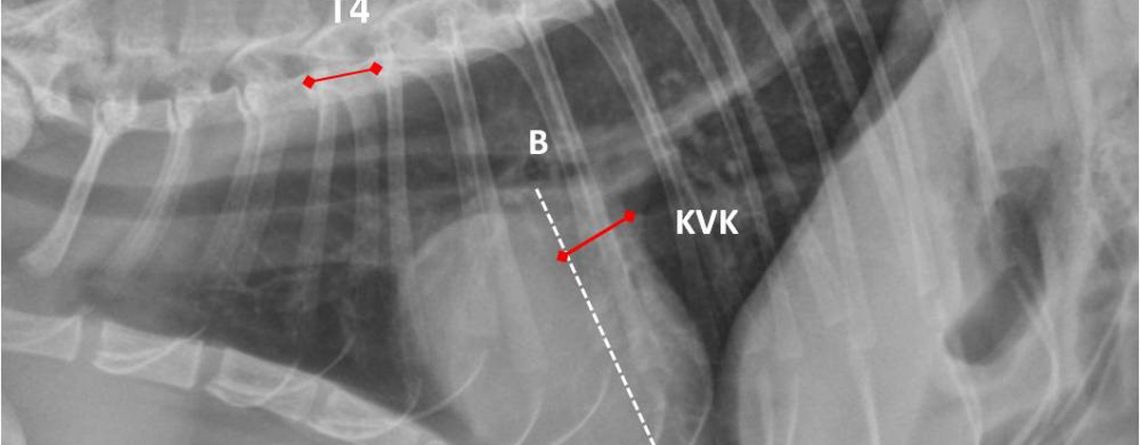

Toraks radyogramlarında küresel biçimdeki kalp görüntüsü, bütün olarak kardiyak ve perikardial oluşumlardan ibaret olduğu için değerlendirilen, kalbin kendisi değil, kalp silüetidir. Kalp silüetinin boyutunun ölçülerek...

Köpeklerde Kalp Silüetinin Objektif Değerlendirilmesi